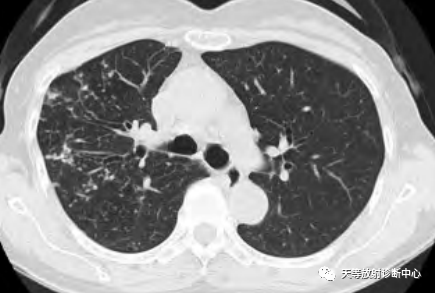

影像学表现:整体观察肺内多发病灶,散在分布,病灶的主要形态为:多发大小不等肺气囊、多发结节共同存在。

1、肺气囊大小不等,张力较大,圆形膨胀感强,周围可见大小不等结节影;

2、病灶主要沿支气管血管束方向分布,部分病灶达到胸膜下;

3、支气管间质增厚;

4、结节影大小不等,小的呈树芽征堆积,大的部分到达胸膜小,具有糊墙征,性格较温和。仔细观察病灶呈四边形、多边形,边缘刀切感,边界模糊。